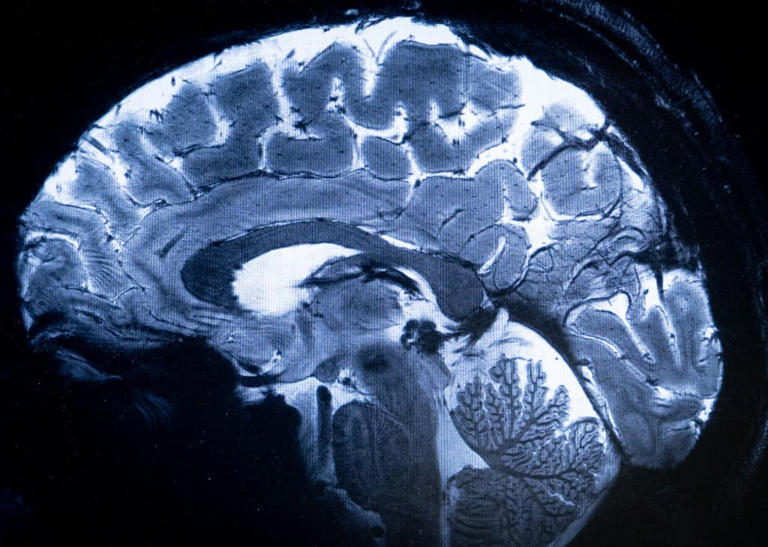

Un cerveau capturé par l'IRM Iseult au CEA, à Gif-sur-Yvette, dans l'Essonne, le 22 mars 2024 (ILLUSTRATION)

Un cerveau capturé par l'IRM Iseult au CEA, à Gif-sur-Yvette, dans l'Essonne, le 22 mars 2024 (ILLUSTRATION)© Alain JOCARD / AFP

Des images du cerveau d'un enfant de six ans d'une précision inédite: des chercheurs du Commissariat à l'énergie atomique (CEA) espèrent, grâce à une innovation technologique, mieux comprendre les troubles du neurodéveloppement et les maladies du cerveau de l'enfant.

Installé depuis 2007 dans un centre de recherche du CEA (Neurospin), sur le plateau de Saclay (Essonne), le puissant IRM qui a produit ces clichés livre déjà des images du cerveau adulte. Adapter cette technologie pour l'utiliser chez l'enfant et obtenir le feu vert des autorités sanitaires pour cet usage a pris plusieurs années de recherche et de développement, ont expliqué les chercheurs mercredi lors d'une conférence de presse.

Un IRM 1,5 à 3 fois plus puissant

Grâce à une meilleure résolution des images et à des contrastes accrus, cet IRM à sept Teslas (unité de mesure nommée en l'honneur du physicien serbe Nikola Tesla) contre 1,5 ou 3 pour les IRM qu'on trouve à l'hôpital dédié à la recherche, permet de voir "les détails fins du cerveau, la vascularisation, le métabolisme cérébral... et son activité à l'échelle individuelle", a-t-il précisé.